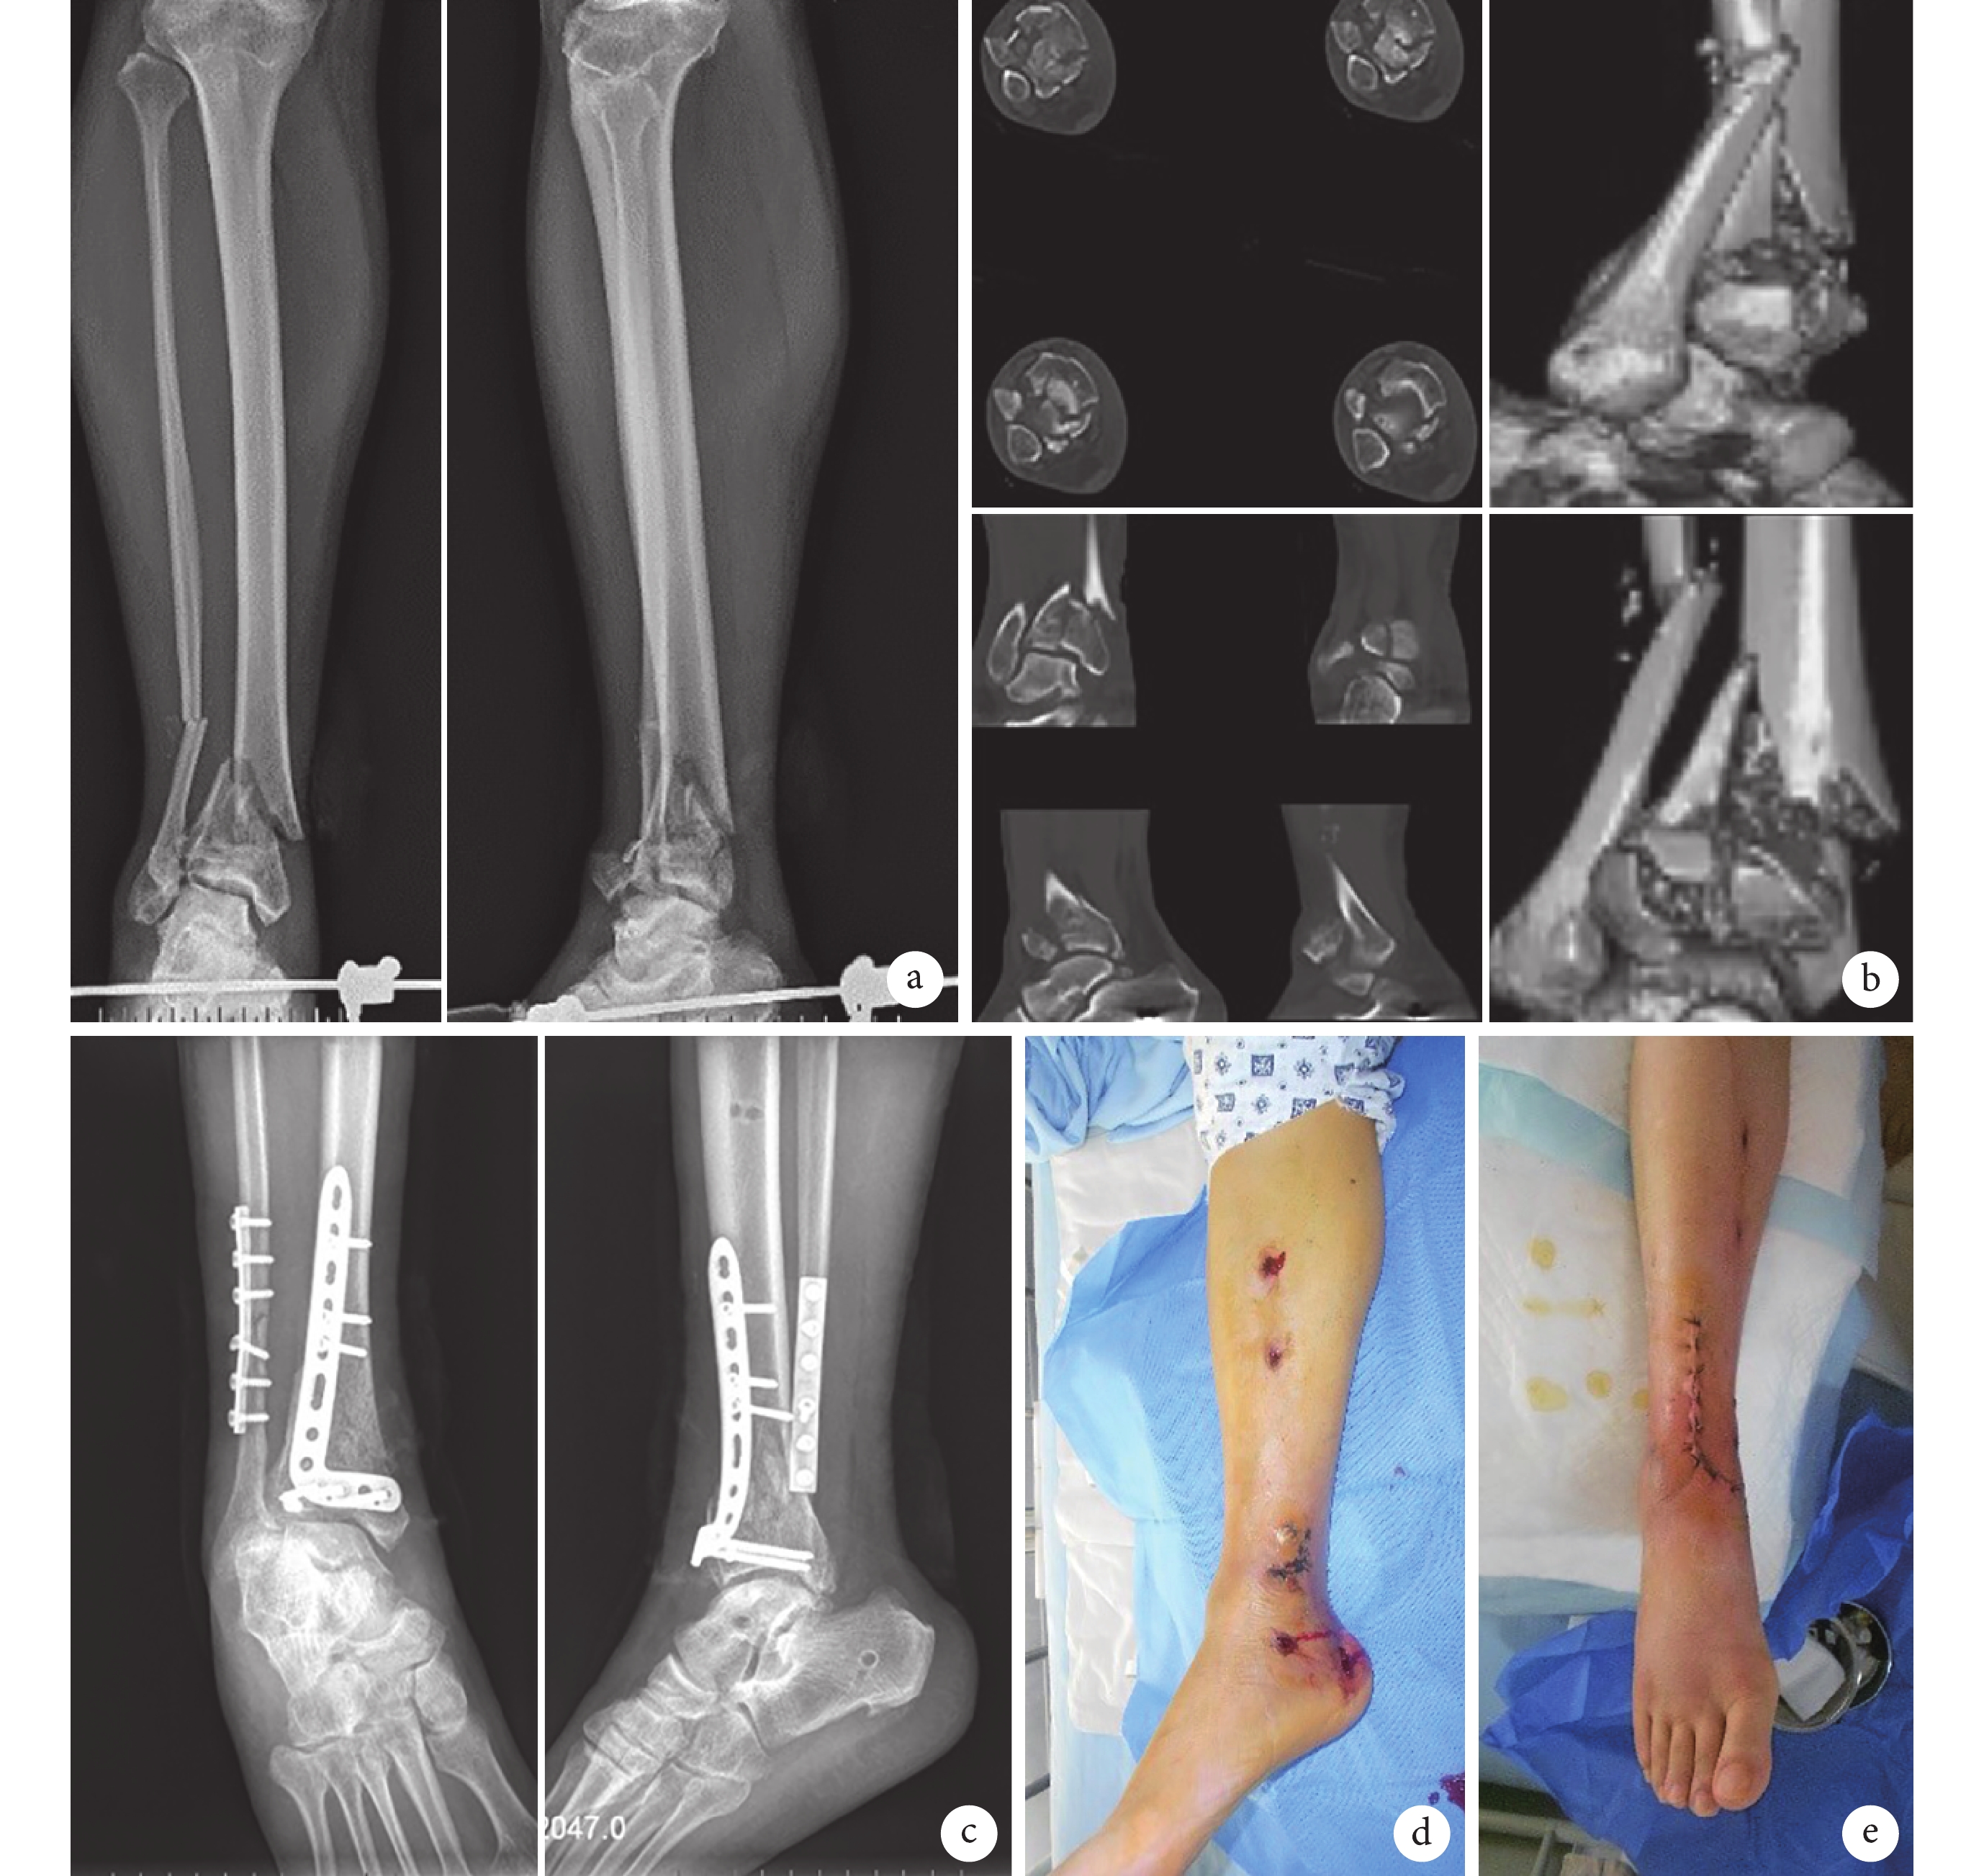

3 典型病例

a. 術前正側位 X 線片示骨折端存在內側成角畸形,斷端不穩;b. 術前 CT 示脛骨關節面嚴重粉碎存在壓縮,Tillaux 骨塊粉碎游離;c. 術后 2 d 正側位 X 線片示脛腓骨骨折畸形糾正,關節面平整,Tillaux 骨塊復位固定良好;d. 術后 21 d 去除外固定架后外觀;e. 二次術后 7 d 踝關節畸形糾正,傷口閉合良好

Figure1. A typical casea. Preoperative anteroposterior and lateral X-ray films showed the fracture present inner angulation deformity and the fracture was unstable; b. Preoperative CT showed severe compression of the tibial articular surface, the Tillaux bone fragments were crushed and dissociated; c. Anteroposterior and lateral X-ray films at 2 days after operation showed that the deformities of tibiofibular fracture were corrected, the articular surface was restored orderly, and the reduction and fixation effect of Tillaux bone block was good; d. The appearance of the injured limb after the external fixator was removed at 21 days after operation; e. At 7 days after the second surgery, the ankle deformity was corrected, the wound was well closed

患者 男,62 歲。因高處墜落致右側 Ruedi-Allgower Ⅲ型 Pilon 骨折,行傷口清創縫合跟骨牽引固定,傷后 2 d 給予抗炎支持治療,傷后 5 d 傷口處紅腫,行腓骨切開復位鋼板內固定、脛骨外固定架固定術,糾正移位并穩定軟組織生長環境,Tillaux 骨塊未同期復位固定。術后繼續抗炎治療,術后 14 d 傷口拆線,術后 21 d 去除外固定架。術后 26 d 行脛骨關節面切開復位、植入同種異體輻照骨粒、鋼板加螺釘內固定術治療,選擇脛骨前外側切口,Tillaux 結節利用伸趾肌腱外側間隙單獨顯露,復位成功并采用單獨螺釘固定 Tillaux 骨塊,完成脛骨穹窿部全部關節面復位;二次手術植骨選擇同種異體輻照骨粒填充壓縮區,修補屈肌支持帶,縫合皮膚。術后 48 h 攝右踝關節正側位 X 線片,采用 Burwell-Chamley 影像學評分系統評價手術復位效果為解剖復位。二次術后 12 d 傷口Ⅰ期愈合拆線,足趾感覺活動正常,足背動脈可觸及,踝關節主動屈曲背伸訓練。患者隨訪 17 個月,未發生感染、皮膚壞死、內固定失效等并發癥。骨折于術后 5 個月獲得愈合,術后 12 個月采用 AOFAS 踝與后足評分評價功能為優;術后 3 個月開始完全負重時 Olerud-Molander 踝關節骨折評分標準評價功能為中,術后 1 年為優。術后 15 個月手術取出內固定物。見圖 1。